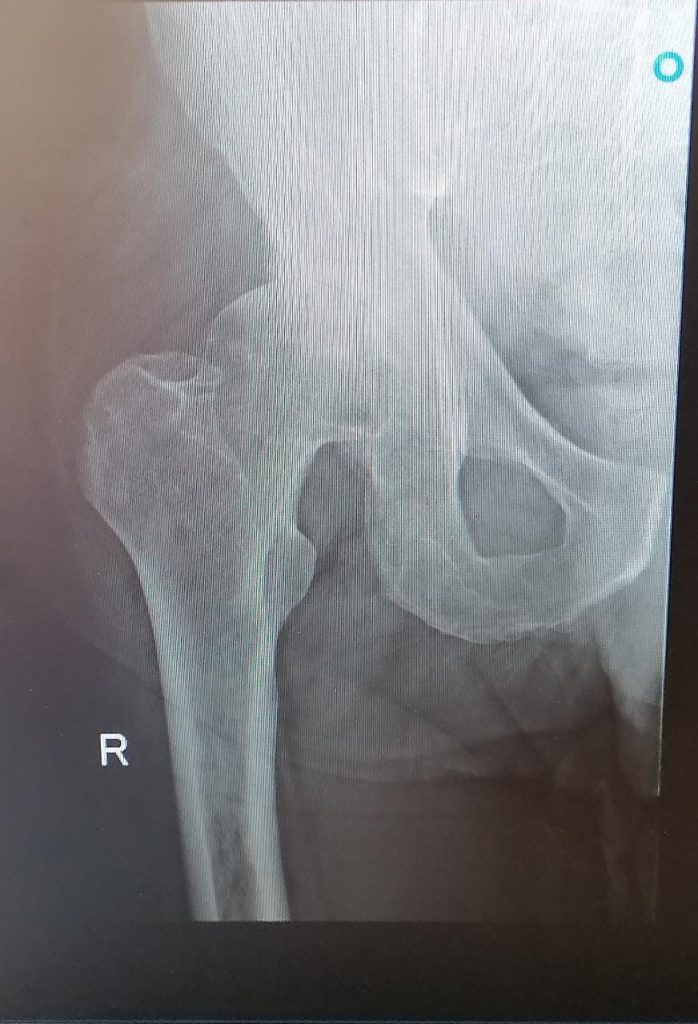

The hip before replacement